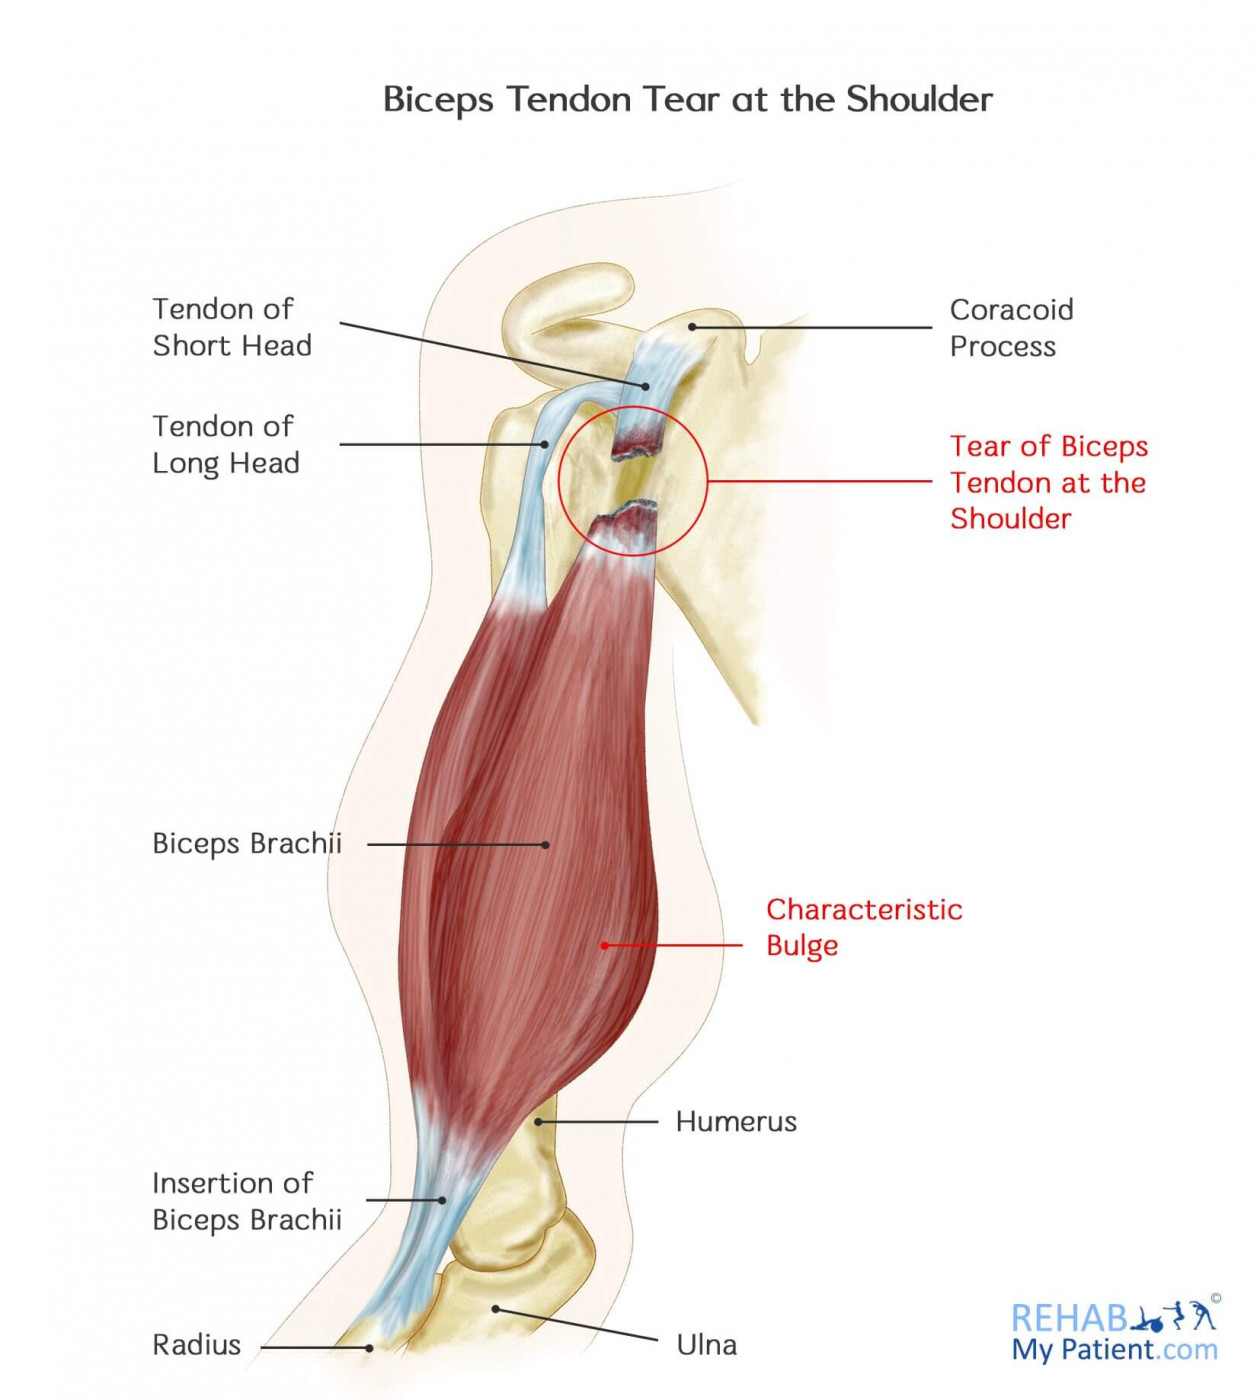

Biceps Tendon Tear at the Shoulder Rehab My Patient

Biceps Tendon Tear Mississauga and Oakville Chiropractor and